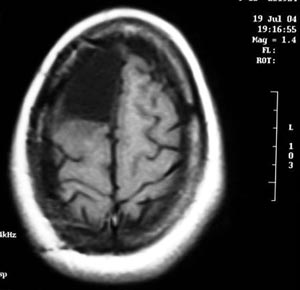

2d) Gliose (processo cicatricial do cérebro)

Figura 52 - Ressonância nuclear magnética pré-operatória.